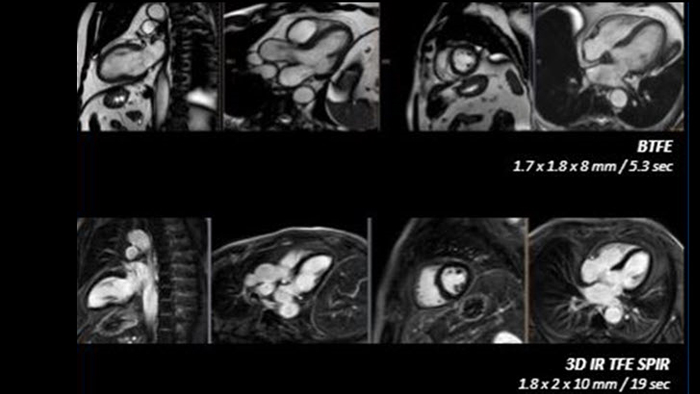

Philips Cardiac MR

Realize the potential of MR throughout the pathway with ultrafast exams, optimized workflow, high-quality diagnostic imaging and enhanced patient comfort.